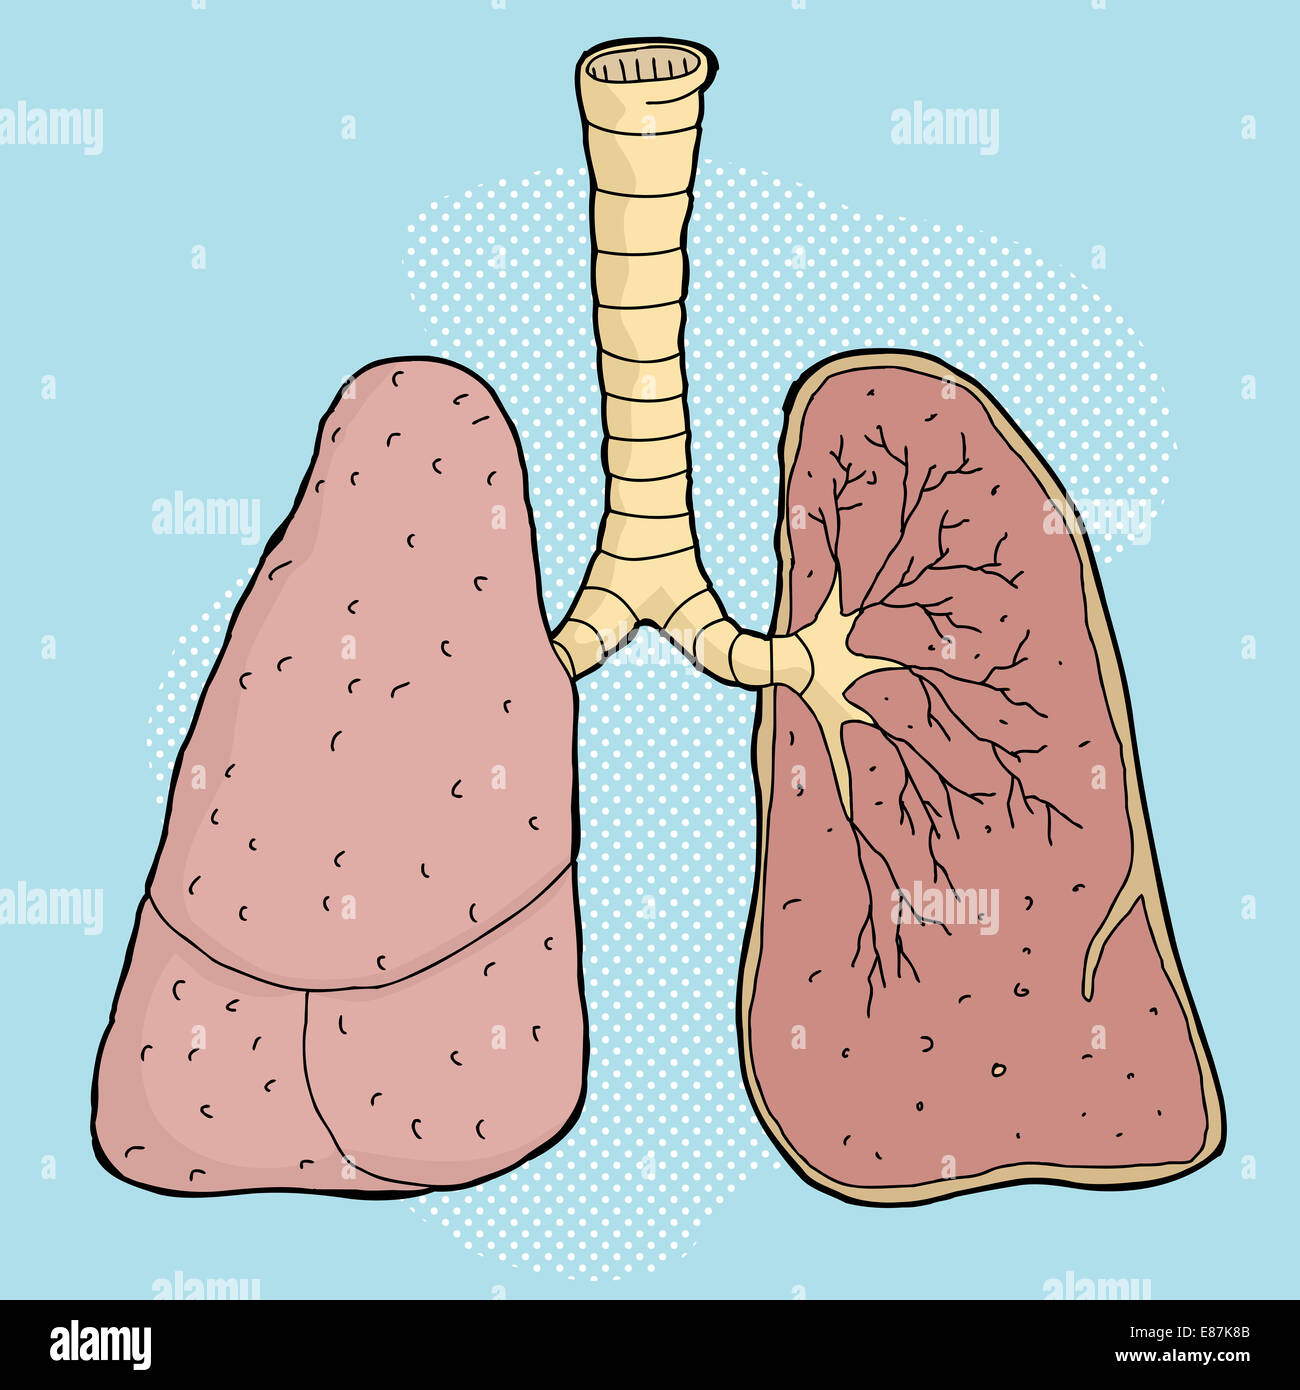

Karikatur der menschlichen Lunge mit Querschnitt Lappen